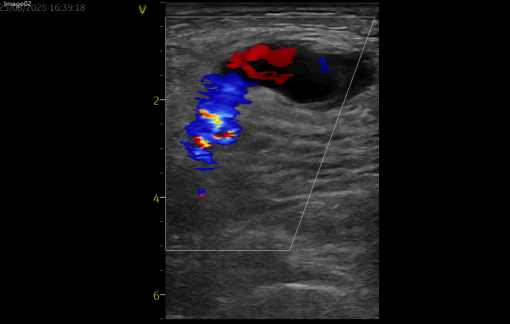

床旁超声检查提示:腹股沟区皮下可见特定范围的无回声区,边界清楚、形态欠规则,可见通道与动脉相连,动脉持续血流灌注;CDFI 示动脉与包块间分流口内可探及双向血流,包块内血流紊乱呈涡流,结合临床症状及检查结果,考虑为假性动脉瘤。

超声引导下凝血酶封堵术已成为临床处理假性动脉瘤的常用微创方式之一。该患者的手术过程顺利,在注射凝血酶 1 分钟后,超声复查显示瘤腔内活动血流消失,瘤体已血栓化,动脉与假性动脉瘤的通道封闭,听诊杂音及体表震颤感均消失。术后患者不适症状得到缓解,恢复顺利,次日出院(此为该患者个体恢复情况,不同患者因病情严重程度、体质、合并基础疾病等差异,恢复周期及效果可能不同)。